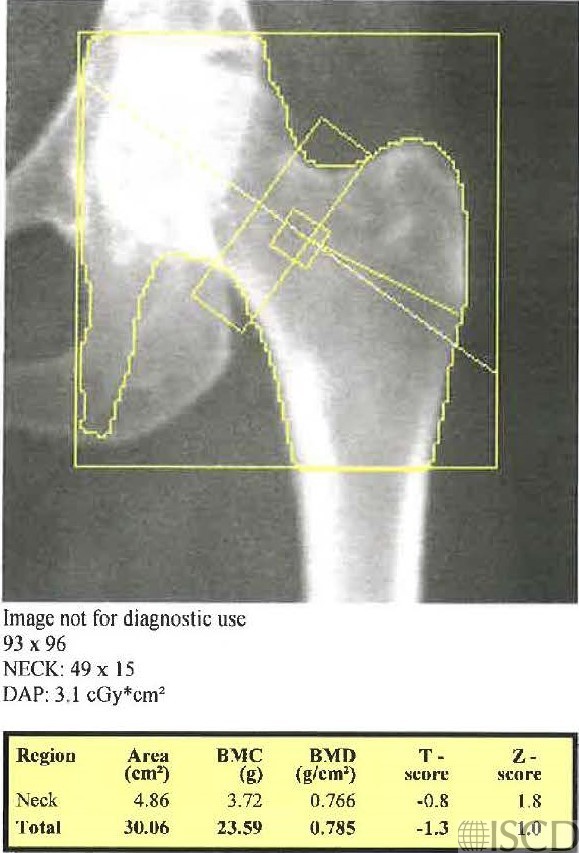

Femoral Neck Box Includes Part of the Ischium

In this image, the femoral neck box includes a portion of the ischium.

In this image, the ischium is deleted so that the femoral neck box data may be used. The length of the femoral neck box has now been changed to the default of 49 pixels.